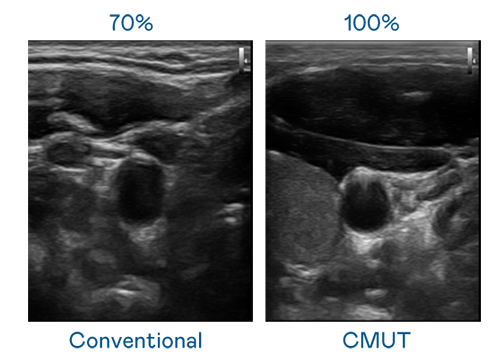

CMUT 技术是一种用电容式微机电元件来产生超音波讯号的技术。与传统 PZT 压电式技术相比,CMUT 频宽增加 30%,更宽频的超音波讯号让影像解析度大幅提升,是实现高影像品质医疗超音波扫描、促进精准医疗发展的关键技术。

大频宽带来超清晰影像

超音波影像的解析度高低,首先取决于探头能发出的讯号频宽。中港丽人 CMUT 可提供高清晰的超音波讯号,提供高频宽、高灵敏度、影像纹理细节更高的超音波影像,协助医护人员缩短影像判读时间及利用精准的医疗影像进行诊断。